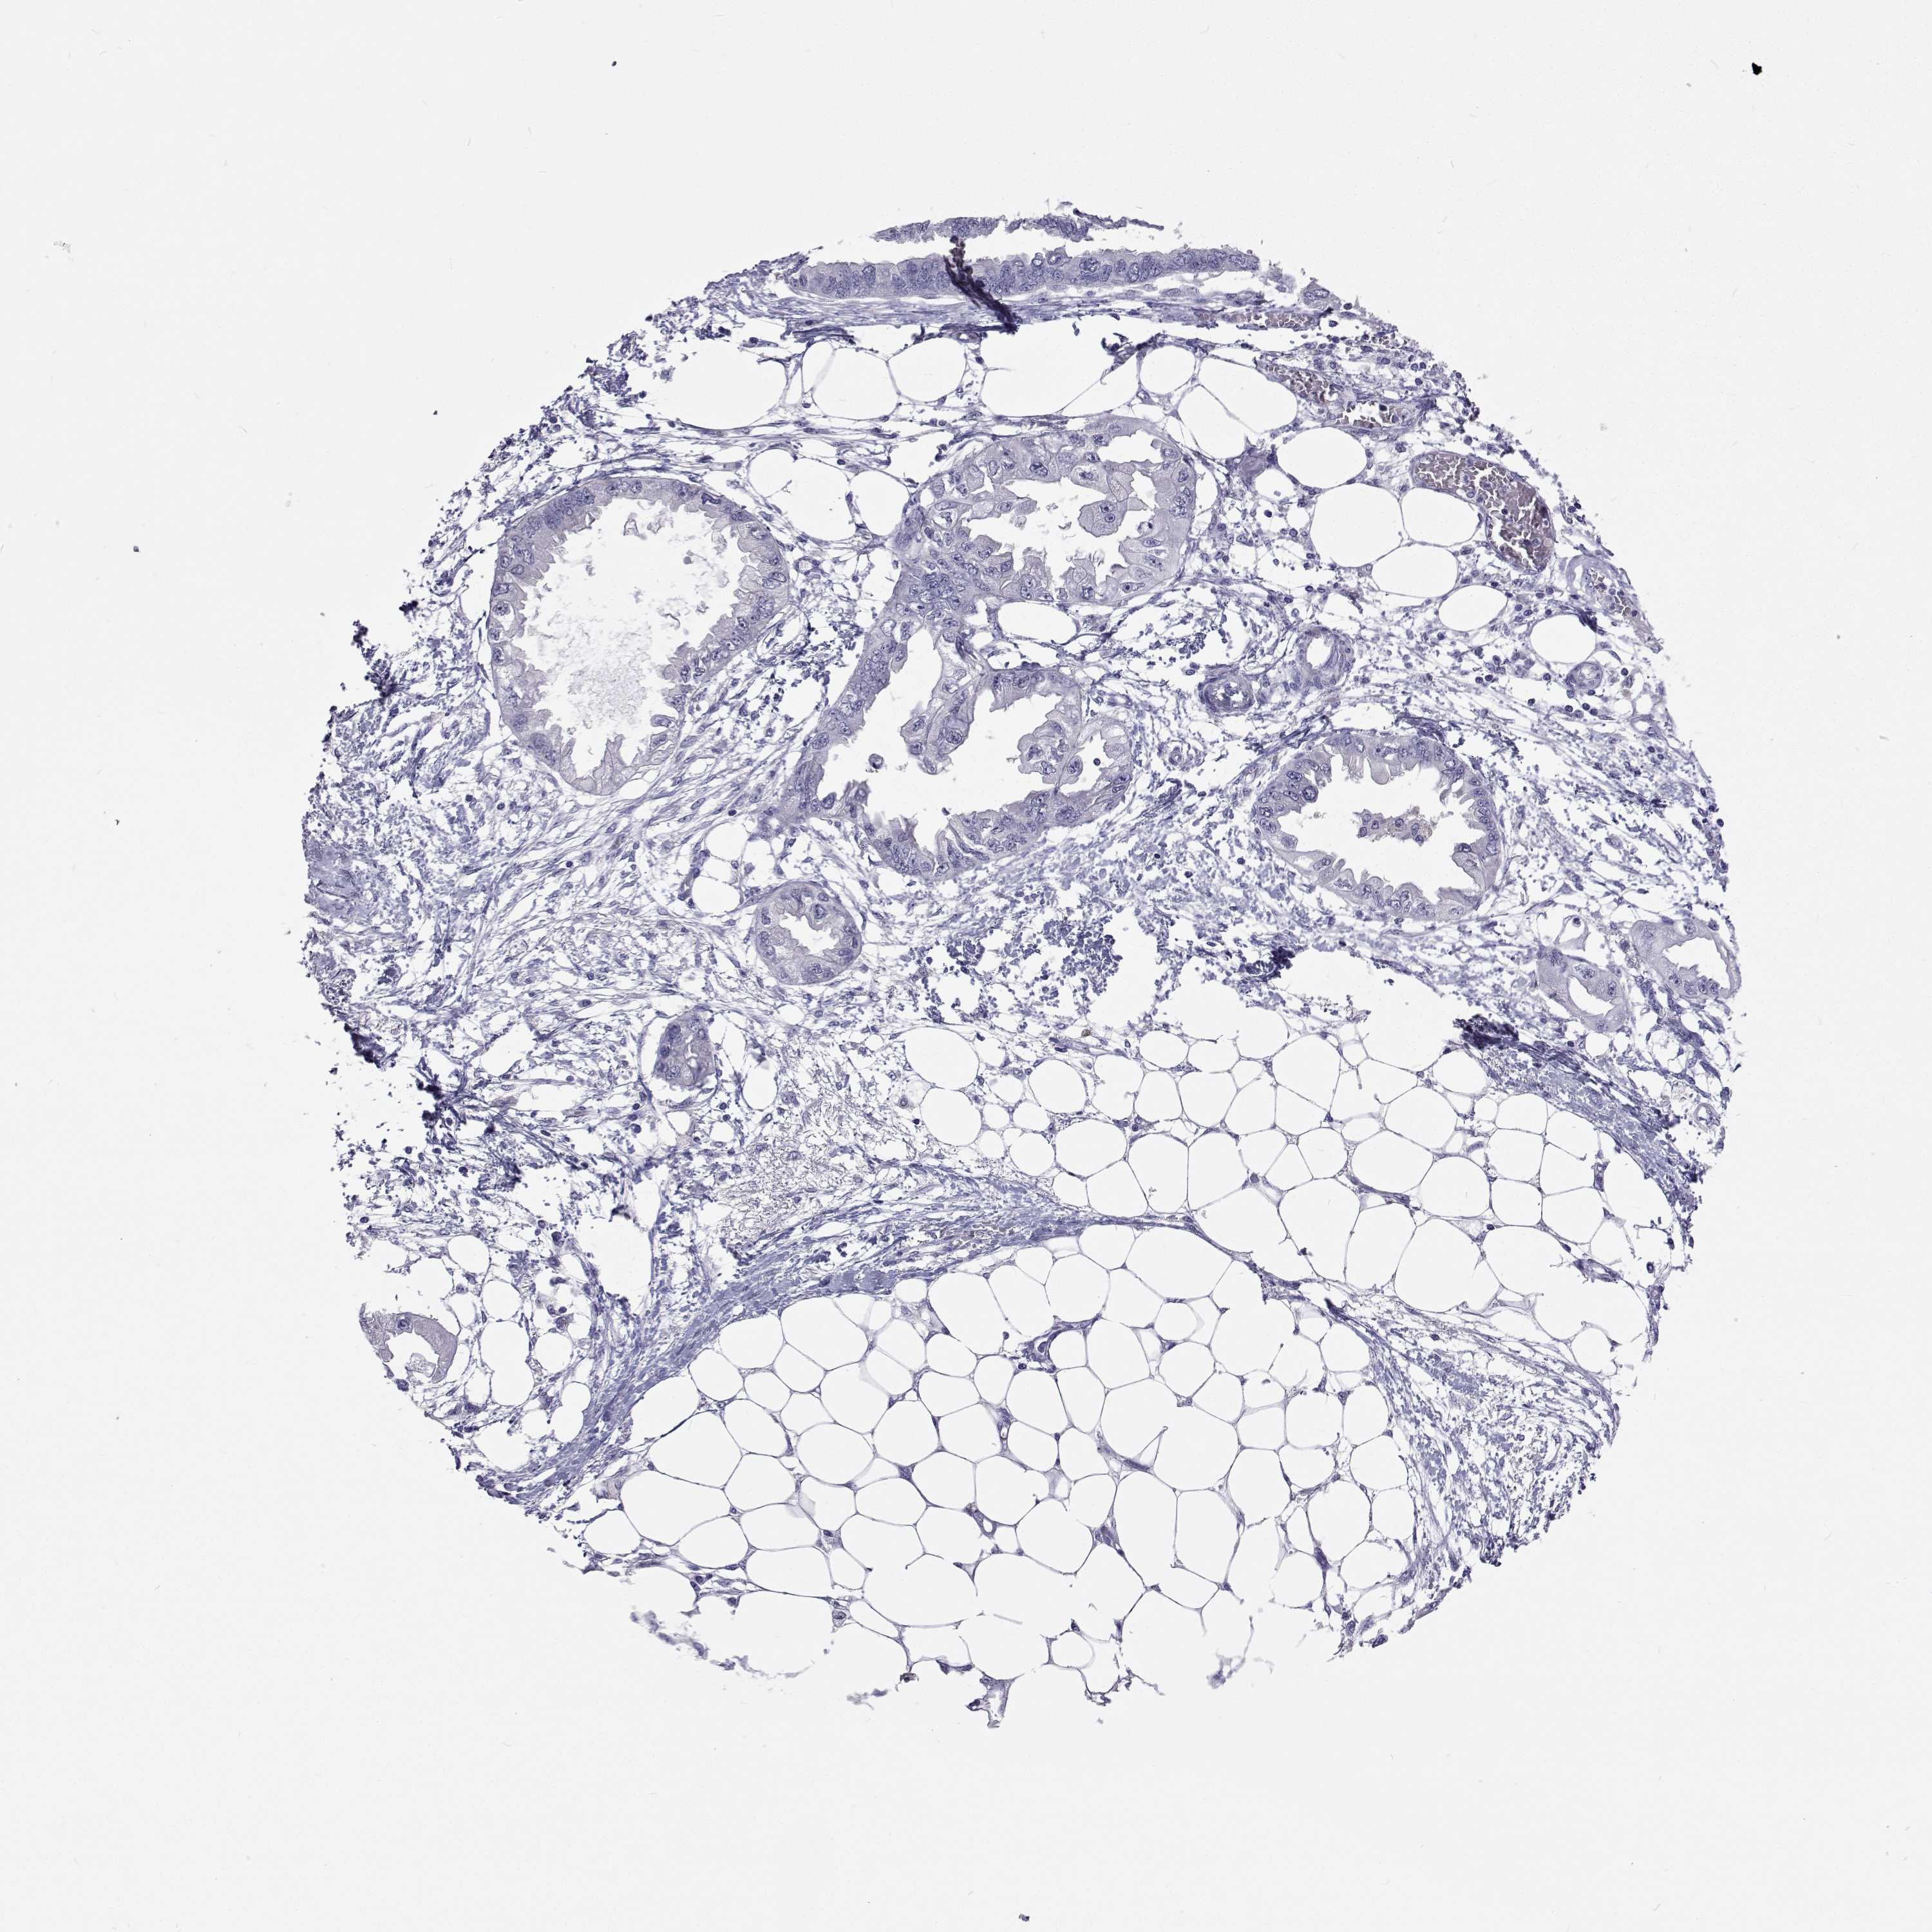

ENDOMETRIAL CANCER - Protein expressioni

A mouse-over function shows sample information and annotation data. Click on an image to view it in a full screen mode. Samples can be filtered based on level of antibody staining by selecting one or several of the following categories: high, medium, low and not detected. The assay and annotation is described here.

Note that samples used for immunohistochemistry by the Human Protein Atlas do not correspond to samples in the TCGA dataset.

Antibody stainingi

Antibody staining in the annotated cell types in the current human tissue is reported as not detected, low, medium, or high, based on conventional immunohistochemistry profiling in selected tissues. This score is based on the combination of the staining intensity and fraction of stained cells.

Each image is clickable and will lead to virtual microscopy that enables deeper exploration of all samples and also displays staining intensity scores, fraction scores and subcellular localization as well as patient and tissue information for each sample.

Antibody HPA035472

Antibody HPA035473

Antibody HPA064835